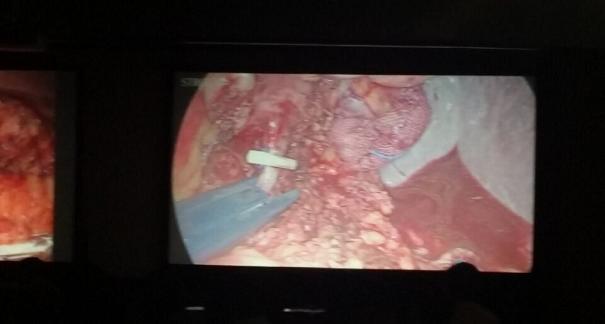

2015年10月23-25日,河北省醫(yī)學(xué)會肝膽外科學(xué)術(shù)年會在河北省石家莊市頤園賓館隆重召開。本次學(xué)術(shù)會議河北省醫(yī)學(xué)會特邀了北京301總院的胡明根教授、天津第一中心醫(yī)院的張雅敏教授、山西醫(yī)大醫(yī)院的趙浩亮、河北醫(yī)科大學(xué)第二醫(yī)院劉建華教授等國內(nèi)知名專家參會。參加會議的醫(yī)院達(dá)100余家,近300名肝膽外科的臨床專家和一線醫(yī)生們親臨會場,在此進(jìn)行廣泛的學(xué)術(shù)交流。25號全天會議安排了五臺手術(shù)視頻演示,全體參會人員進(jìn)行觀摩,并實時提問,進(jìn)行手術(shù)交流。演示手術(shù)包括腹腔鏡胰、十二指腸切除術(shù)、腹腔鏡左、右半肝切除術(shù)、腹腔鏡門脈高壓癥的治療、兩鏡或三鏡聯(lián)合膽石癥的治療、開腹胰、十二指腸切除術(shù)、手術(shù)演示中多次使用了我公司產(chǎn)品速豐(可吸收止血結(jié)扎夾),產(chǎn)品使用滿意度受到專家們的一致好評。